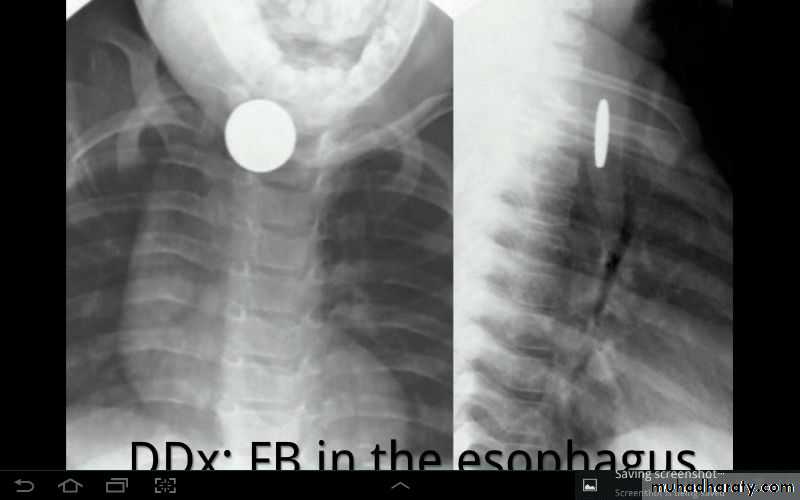

What is the difference?

Differential diagnosis?